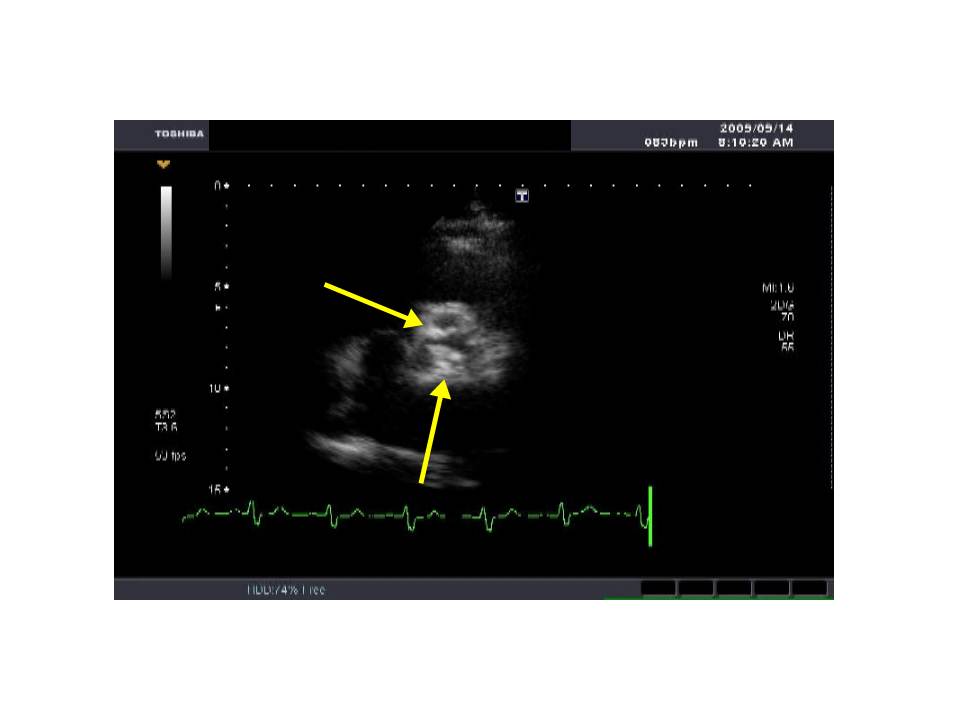

二尖弁に伴う重症ASの1例

出典

img

1: 著者提供